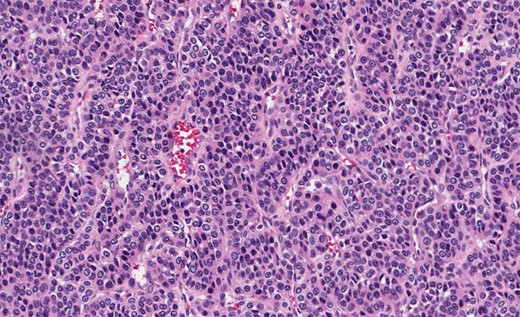

Gastric GT. Note the well-circumscribed submucosal lesion surrounding small vessels (H&E stain, ×20).

Grossly, GTs are multinodular, soft and rubbery on sectioning [3]. The cellular nodules are separated by streaks of gastric smooth muscle, which also surrounds the tumor [3]. Histologic features are central round to oval nuclei with inconspicuous nucleoli and clear to eosinophilic cytoplasm with distinct cell borders [1] (Figs. 3 and 4). GTs are positive for α-smooth muscle actin, vimentin, calponin and caldesmon. They are most often negative for CD117, CD34, chromogranin and synaptophysin [3, 6].

Gastric GT. Note central round or oval nuclei with clear, eosinophilic cytoplasm (H&E stain, ×200).